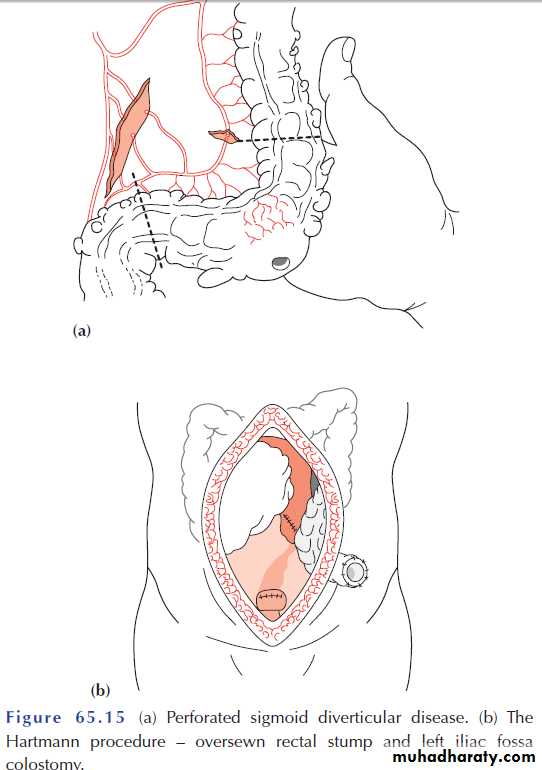

Computerized tomography scan showing a segment of thickened sigmoid colon with a paracolic abscess (arrow) in a patient with diverticulitis.

This will demonstrate not only the diverticula but also any associated pericolic abscess .Barium enemas & sigmoidoscopy are usually reserved for patients who have recovered from an attack of acute diverticulitis, for fear of causing perforation or peritonitis.

Water-soluble contrast enemas may, however, be helpful in sorting out patients with large bowel obstruction. Barium radiology is carried out to exclude a carcinoma and to assess the extent of the disease. Where the sigmoid colon is thickened and narrowed, a 'saw-tooth’ appearance may be seen.